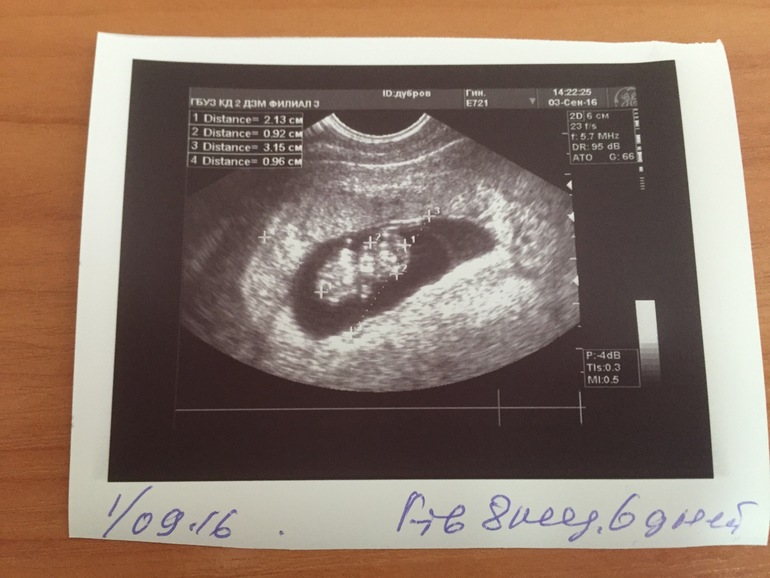

вчера вечером меня сухо неприятно вырвало, утром как обычно желчью но коричневого цвета, кровью, фи, неприятно так было как вспомню, и утром еще увидела светло светло коричневые вылеления... оттуда, и резало снизу живота немного, обо всем этом рассказала и терапефт отправила без очереди меня к гинекологу моей, посмотрела, все чисто, выделения светленькие хорошие, начала щупать живот и говорит матка как на 12 недель, мол по срокам 9 а маткк большая, хотя узи и скрининг уже вчера она мне назначила на 14.09, в общем прямо с ее кресла отправила меня на узи без очереди что бы посмотреть сколько малышу нашему, что бы не пролететь со скринингом, пришла на узи, минуту посмотрела, сердце на 2 сек всключила и даже не видела малыша своего) только уряяя, фото на память оставила))) по узи ням 8 недель и 6 дней) 1,9 см от макушечки до попки😌😌😌 такой масечка любименький уже)